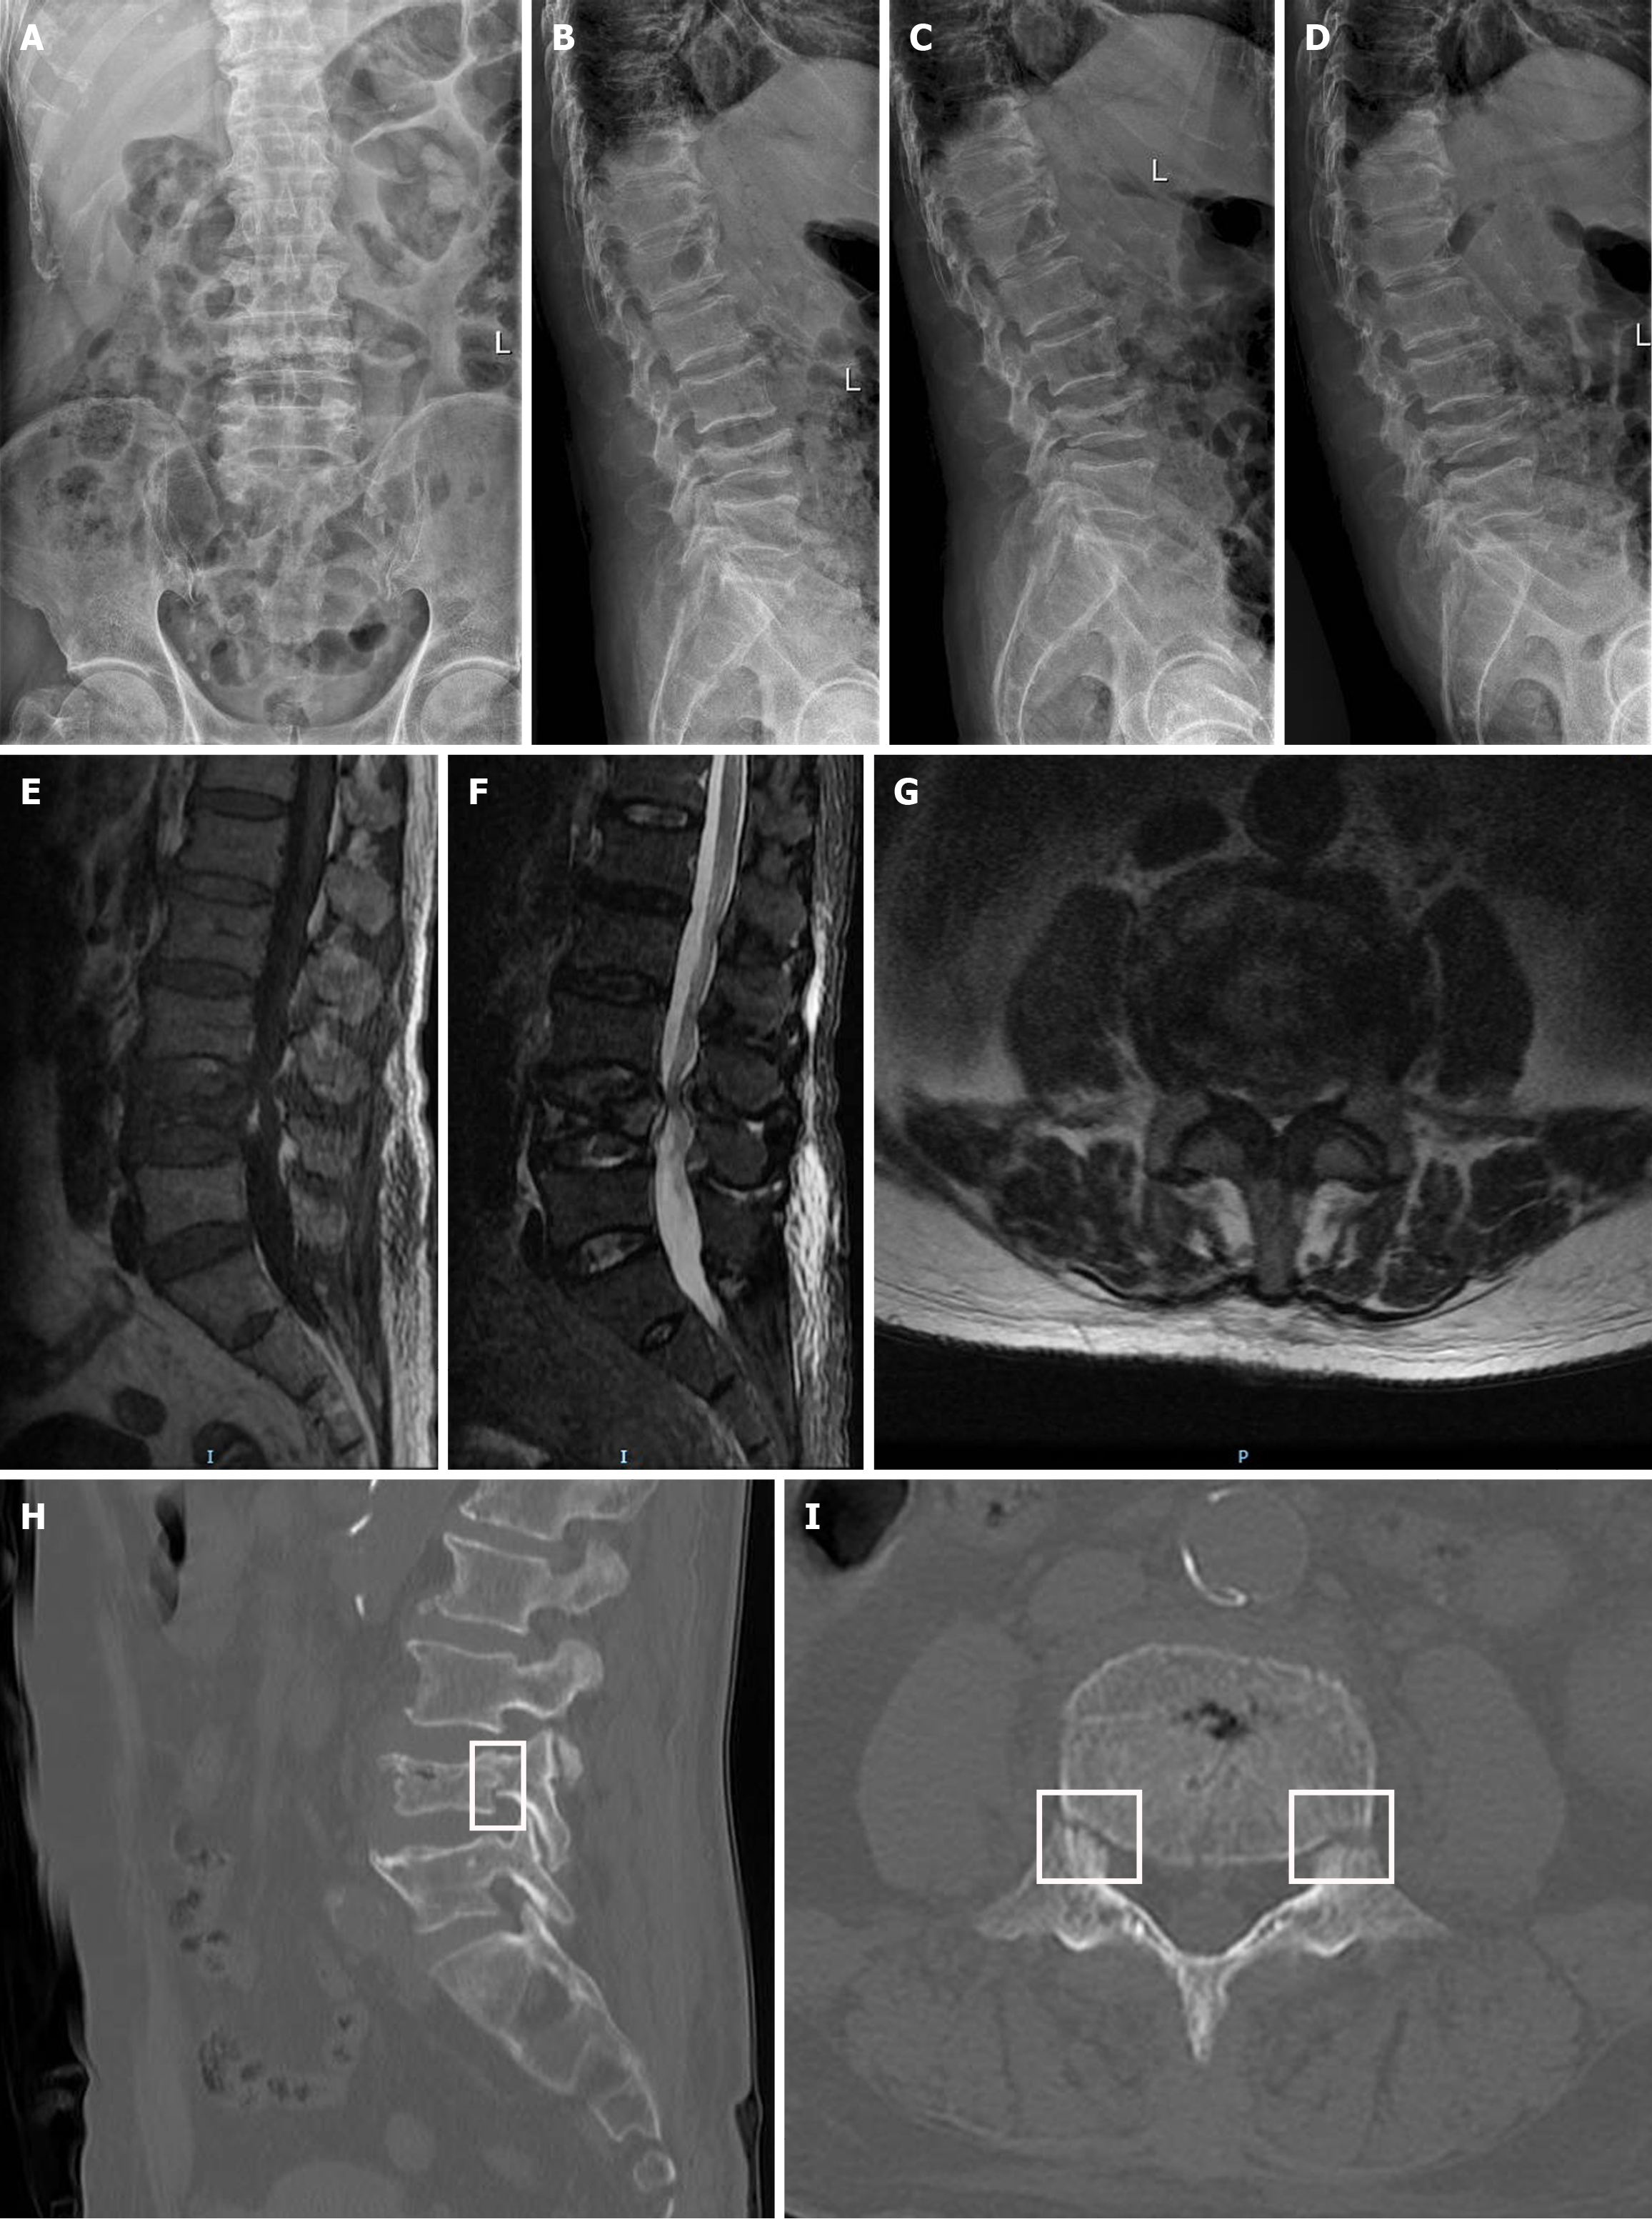

Figure 1 Preoperative imaging examination.

A-D: Preoperative lumbar spine digital radiography in anteroposterior, lateral, and flexion-extension views, indicating compression change of L4 vertebrae; E-G: Preoperative magnetic resonance imaging included T1-weighted imaging (E), short tau inversion recovery imaging (F), and axial images at the inferior margin of the L3/4 intervertebral disc level (G), indicating bone marrow edema of L4 vertebrae and spinal canal stenosis at the L3/4 intervertebral disc level; H and I: Sagittal (H) and axial (I) views of the L4 vertebra on preoperative computed tomography, the pedicle fracture sites were marked within the white frame.